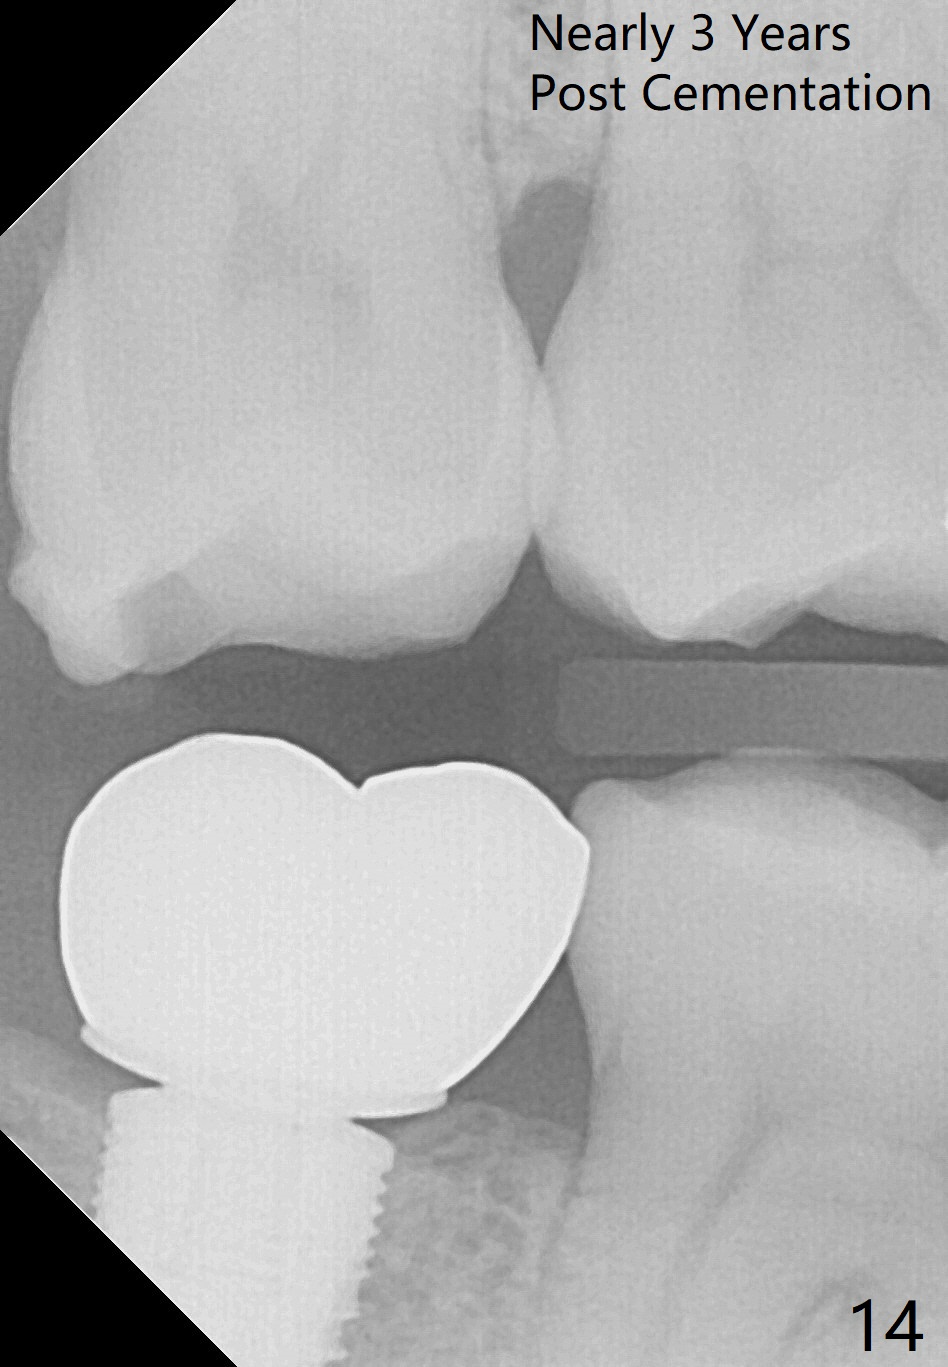

The wound heals uneventfully (Fig.8,9: taken 3 months postop). When an abutment is placed, there is no clearance for a crown. Two mini-implants are placed for the tooth #2 intrusion (Fig.10,11). Four months later, segmental orthodontic appliance is added because of lack of result of intrusion and buccoversion of the tooth #2 (Fig.12). Two months later, all of orthodontic treatment is terminated at the request of the patient. After heavy reduction of the tooth #2, a crown is cemented. Fig.13 (panoramic X-ray) is taken 11 months post cementation. There is no bone loss nearly 3 years post cementation (Fig.14).